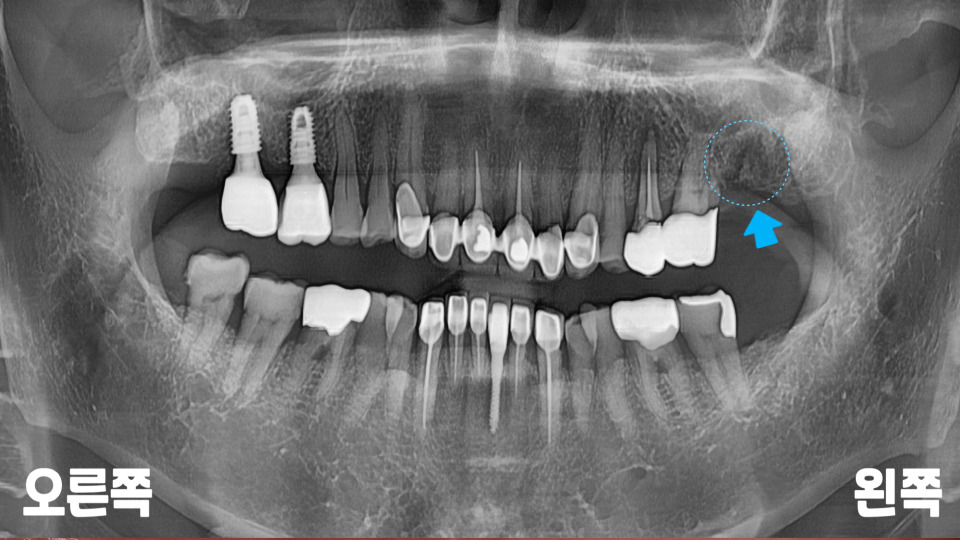

왼쪽 위 작은 어금니 주변으로

거뭇한 뿌리 끝 염증이

확인되는데요.

예전에 신경 치료했던

치아 속으로 탈이 난

모습입니다.

근단부 끝까지

제거 및 충전이

되지 않아 보여

재신경치료(re-endo)를

시도해 볼 수도 있겠지만,

심한 병소로 주변 뼈가

많이 녹아 있는 모습에

자연 치아를 살리기는

무리가 있어 보입니다.

실제로 잇몸 부근을

측면에서 누르면

살짝 고름이 나오기까지

했는데요.

빠른 시일 내에

발치하는 것이 좋겠습니다.

또한 파노라마로

전체적인 입 속 체크를

해 보았을 때,

왼쪽 맨 끝으로 아직

뼈가 덜 아문 흔적이 있습니다.